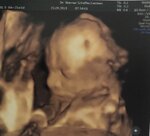

Baby Hamza

Geburt 02.02.2020